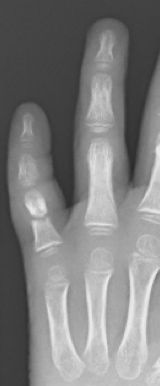

Se trata de una deformidad del dedo con flexo de la falange distal por lesión del tendón extensor o un arrancamiento óseo en la base de la tercera falange. Es más frecuente en la adolescencia, aunque puede ocurrir a cualquier edad. El dedo en martillo tendinoso por rotura del extensor sin lesión ósea se trata con una férula con la IFD en extensión durante 8 semanas. Se debe realizar un tratamiento quirúrgico cuando existe fractura con un fragmento avulsionado superior al 40% de la superficie articular pudiendo realizar diferentes técnicas quirúrgicas. (Figura 19)

Figura 19: a, b- Fractura de la falange distal desplazada con avulsión tendón extensor. Tratamiento quirúrgico mediante técnica de Ishiguro